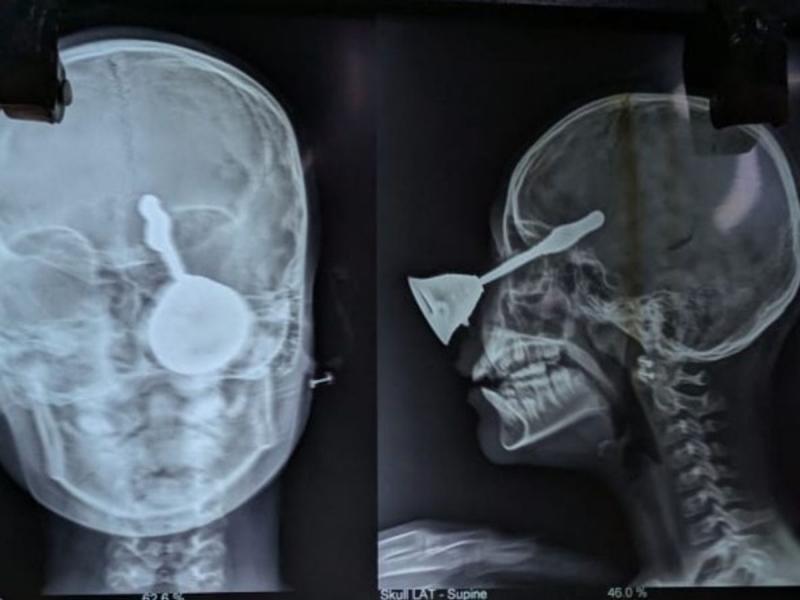

रायपुर (खबरगली) छत्तीसगढ़ के बिलासपुर के मस्तूरी में दिवाली के दिन 10 साल की बच्ची काव्या का खेल-खेल में पैर फिसल गया और पूजा के लिए रखी घंटी उसकी आंख में घुस गई। घंटी बच्ची के दिमाग तक पहुंच गई। परिजनों ने तुरंत उसे नजदीकी अस्पताल में भर्ती कराया। हालत बिगड़ने पर रातों-रात उसे रायपुर एम्स ले जाया गया।

यहां विशेषज्ञों ने जटिल सर्जरी कर घंटी निकाली। हालांकि, काव्या की एक आंख क्षतिग्रस्त हो गई है और मस्तिष्क पर भी बुरा असर पड़ा है। डॉक्टर लगातार उसकी निगरानी कर रहे हैं और फिलहाल उसकी हालत नाजुक बनी हुई है। मस्तिष्क पर असर के कारण आगे भी उसका विशेष ध्यान रखना पड़ेगा।